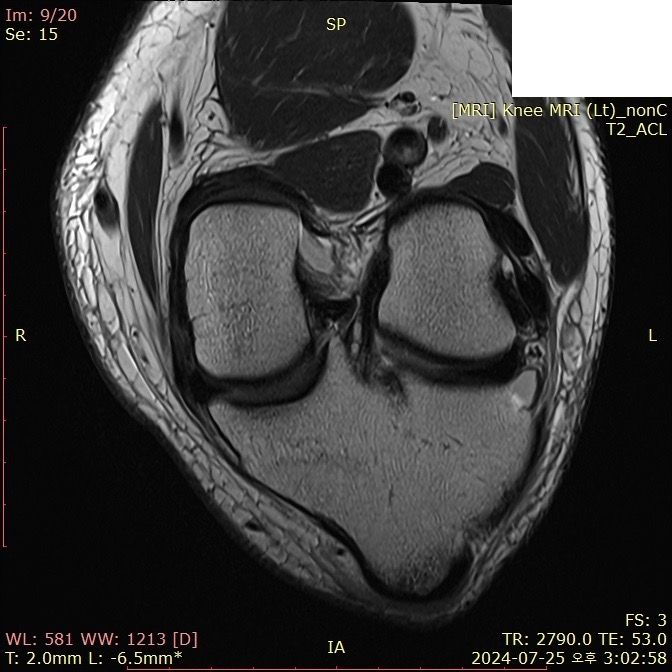

무릎 ACL(전방십자인대) 확인 부탁드려요

아스팔트에 무릎을 부딪쳐 심하게 부어서 mri 찍어봤는데 슬개골 비변위성 골절 판독 받은 건 기억 나는데, 인대는 기억이 잘 안나서 여쭤 봅니다..

전방십자인대 괜찮은가요...??ㅠㅠ

Mri에서 슬개골 비변위성 골절이 판독되었다면 일반적으로 전방십자인대에 대한 언급이 없다면 괜찮을 가능성이 큽니다. 하지만 정확한 진단은 의사와 상담을 통해 확인하는 것이 중요합니다.